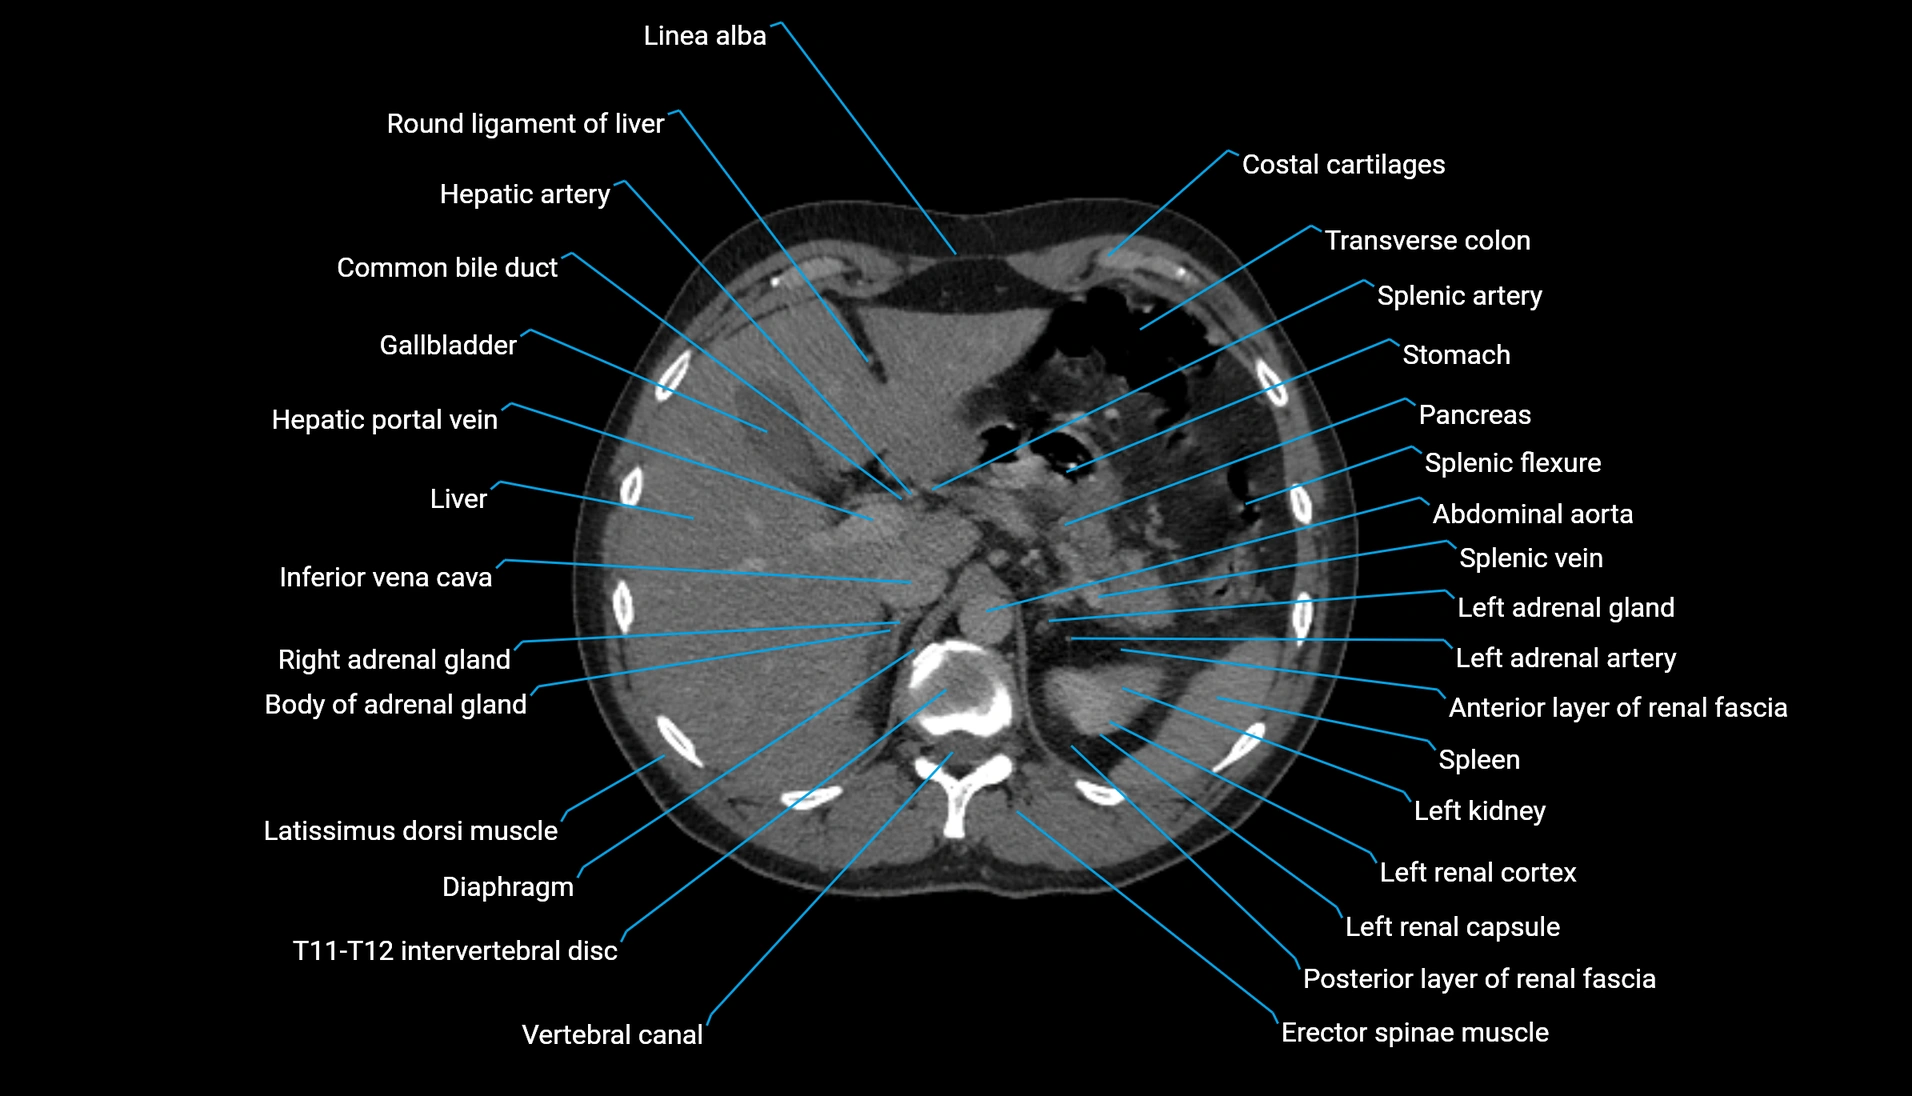

CT Appearance

Non-contrast CT:

-

Demonstrates cortical bone of acetabular rim in excellent detail

Detects fractures, dysplasia, retroversion, or bony overcoverage (pincer impingement)

3D reconstructions used in preoperative hip surgery planning

CT VRT 3D image

CT image